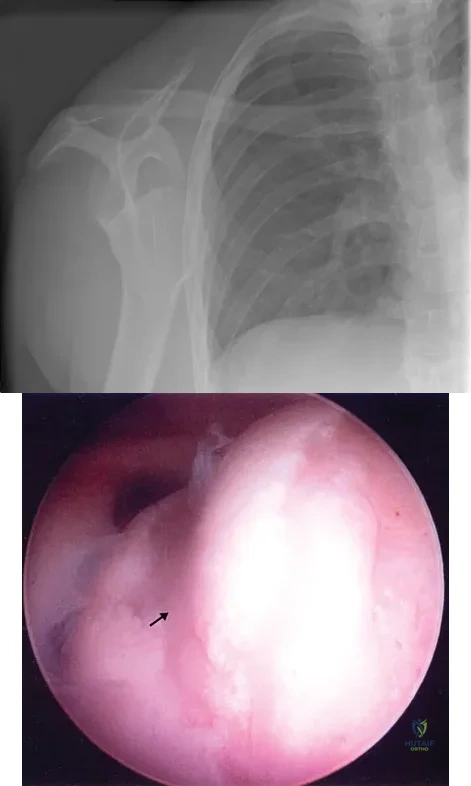

Figure 4a shows the radiograph of a 20-year-old man who has an injury to the right shoulder. Figure 4b shows an arthroscopic view (posterior portal). The arrow points to a

Explanation